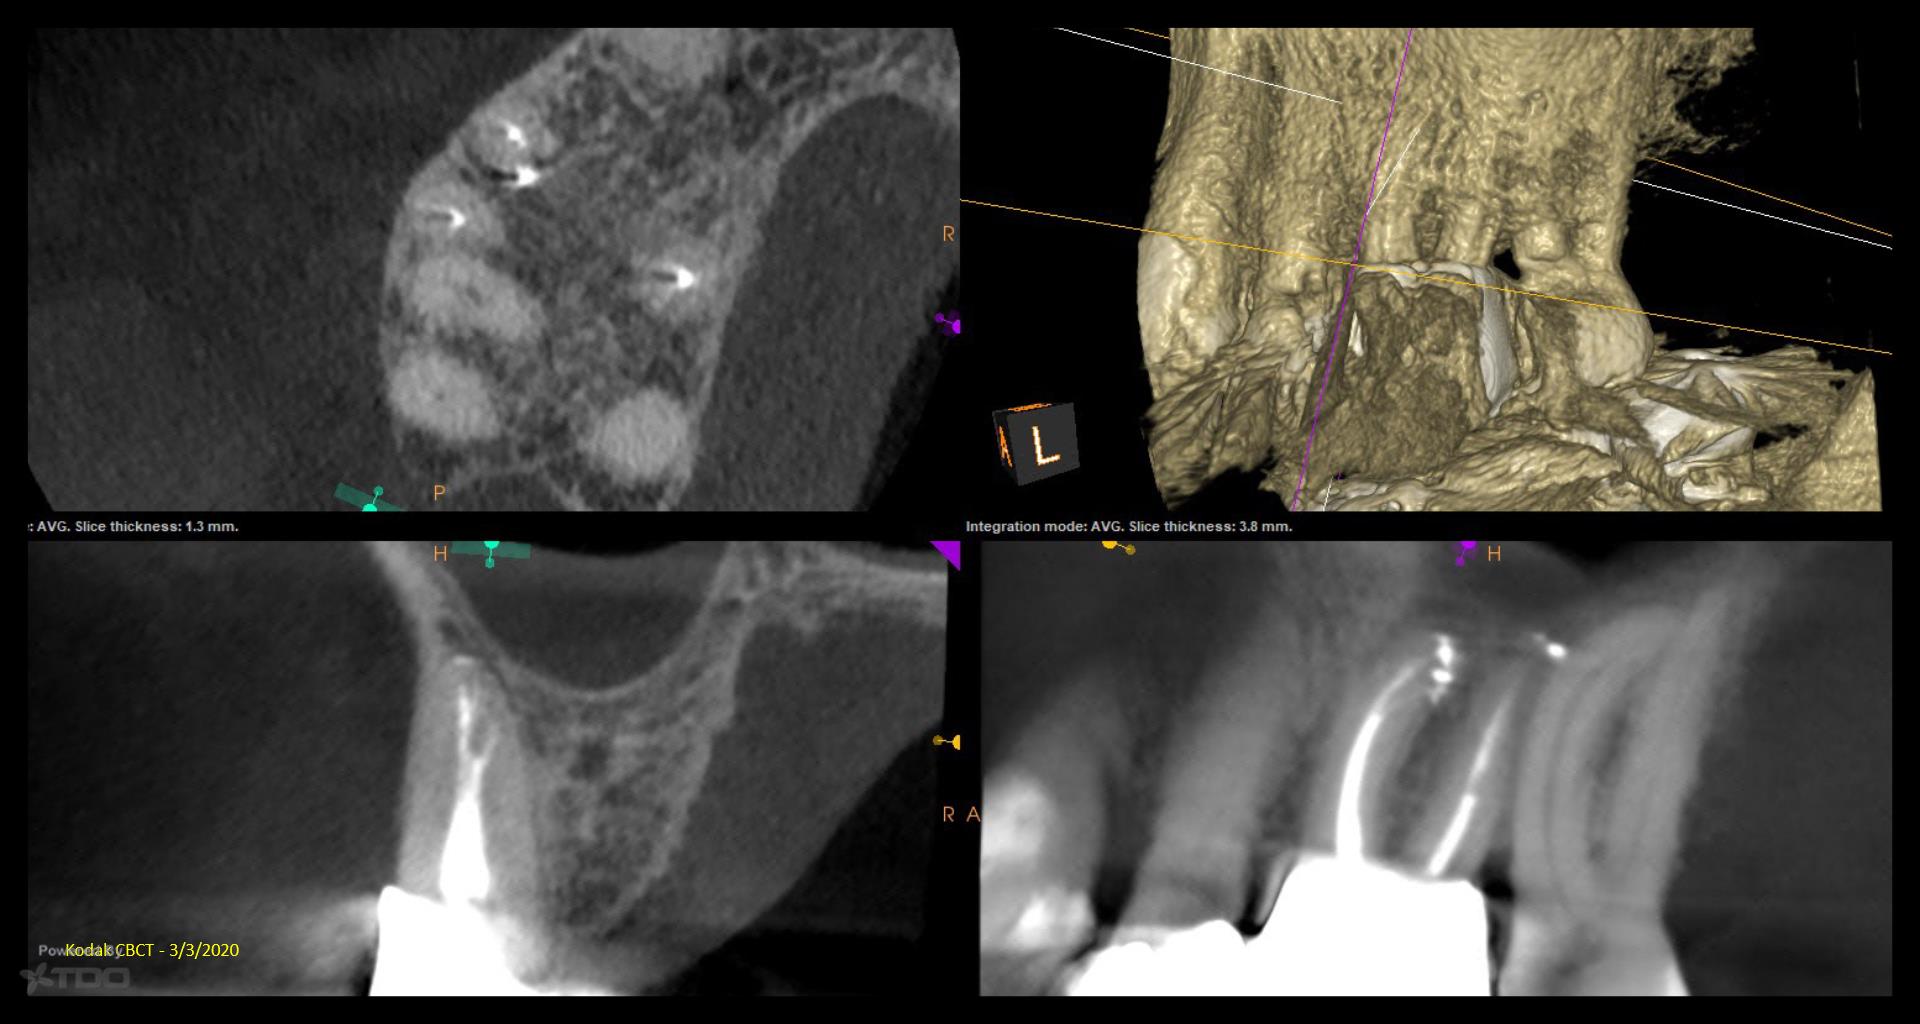

Fascinating read about the 1 year GW recall. The visual aid teeth cleaning image by doctor elevates the comprehension of the subject matter and makes the content more engaging. Fence Decking Supplier in Toms River NJ

Fascinating read about the 1 year GW recall. The visual aid teeth cleaning image by doctor elevates the comprehension of the subject matter and makes the content more engaging.